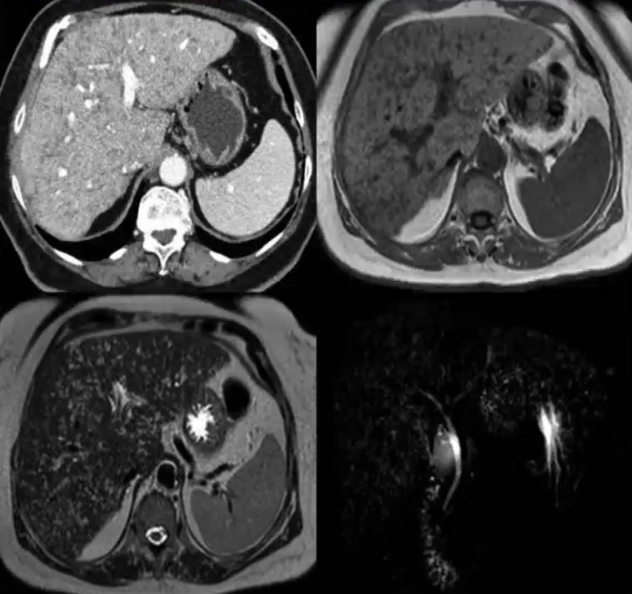

❖ CT:平扫主要表现为肝内多发低密度的小囊状病灶

❖ MRI:T1WI低信号,T2WI高信号,DWI等信号

❖ MRCP:所有病灶呈明显囊状高信号,沿胆管树分布,但不与胆管树相互交通

❖ 增强扫描多无强化,少数病灶可出现环形强化,认为是由于病灶压迫邻近肝组织或者炎性细胞浸润所致